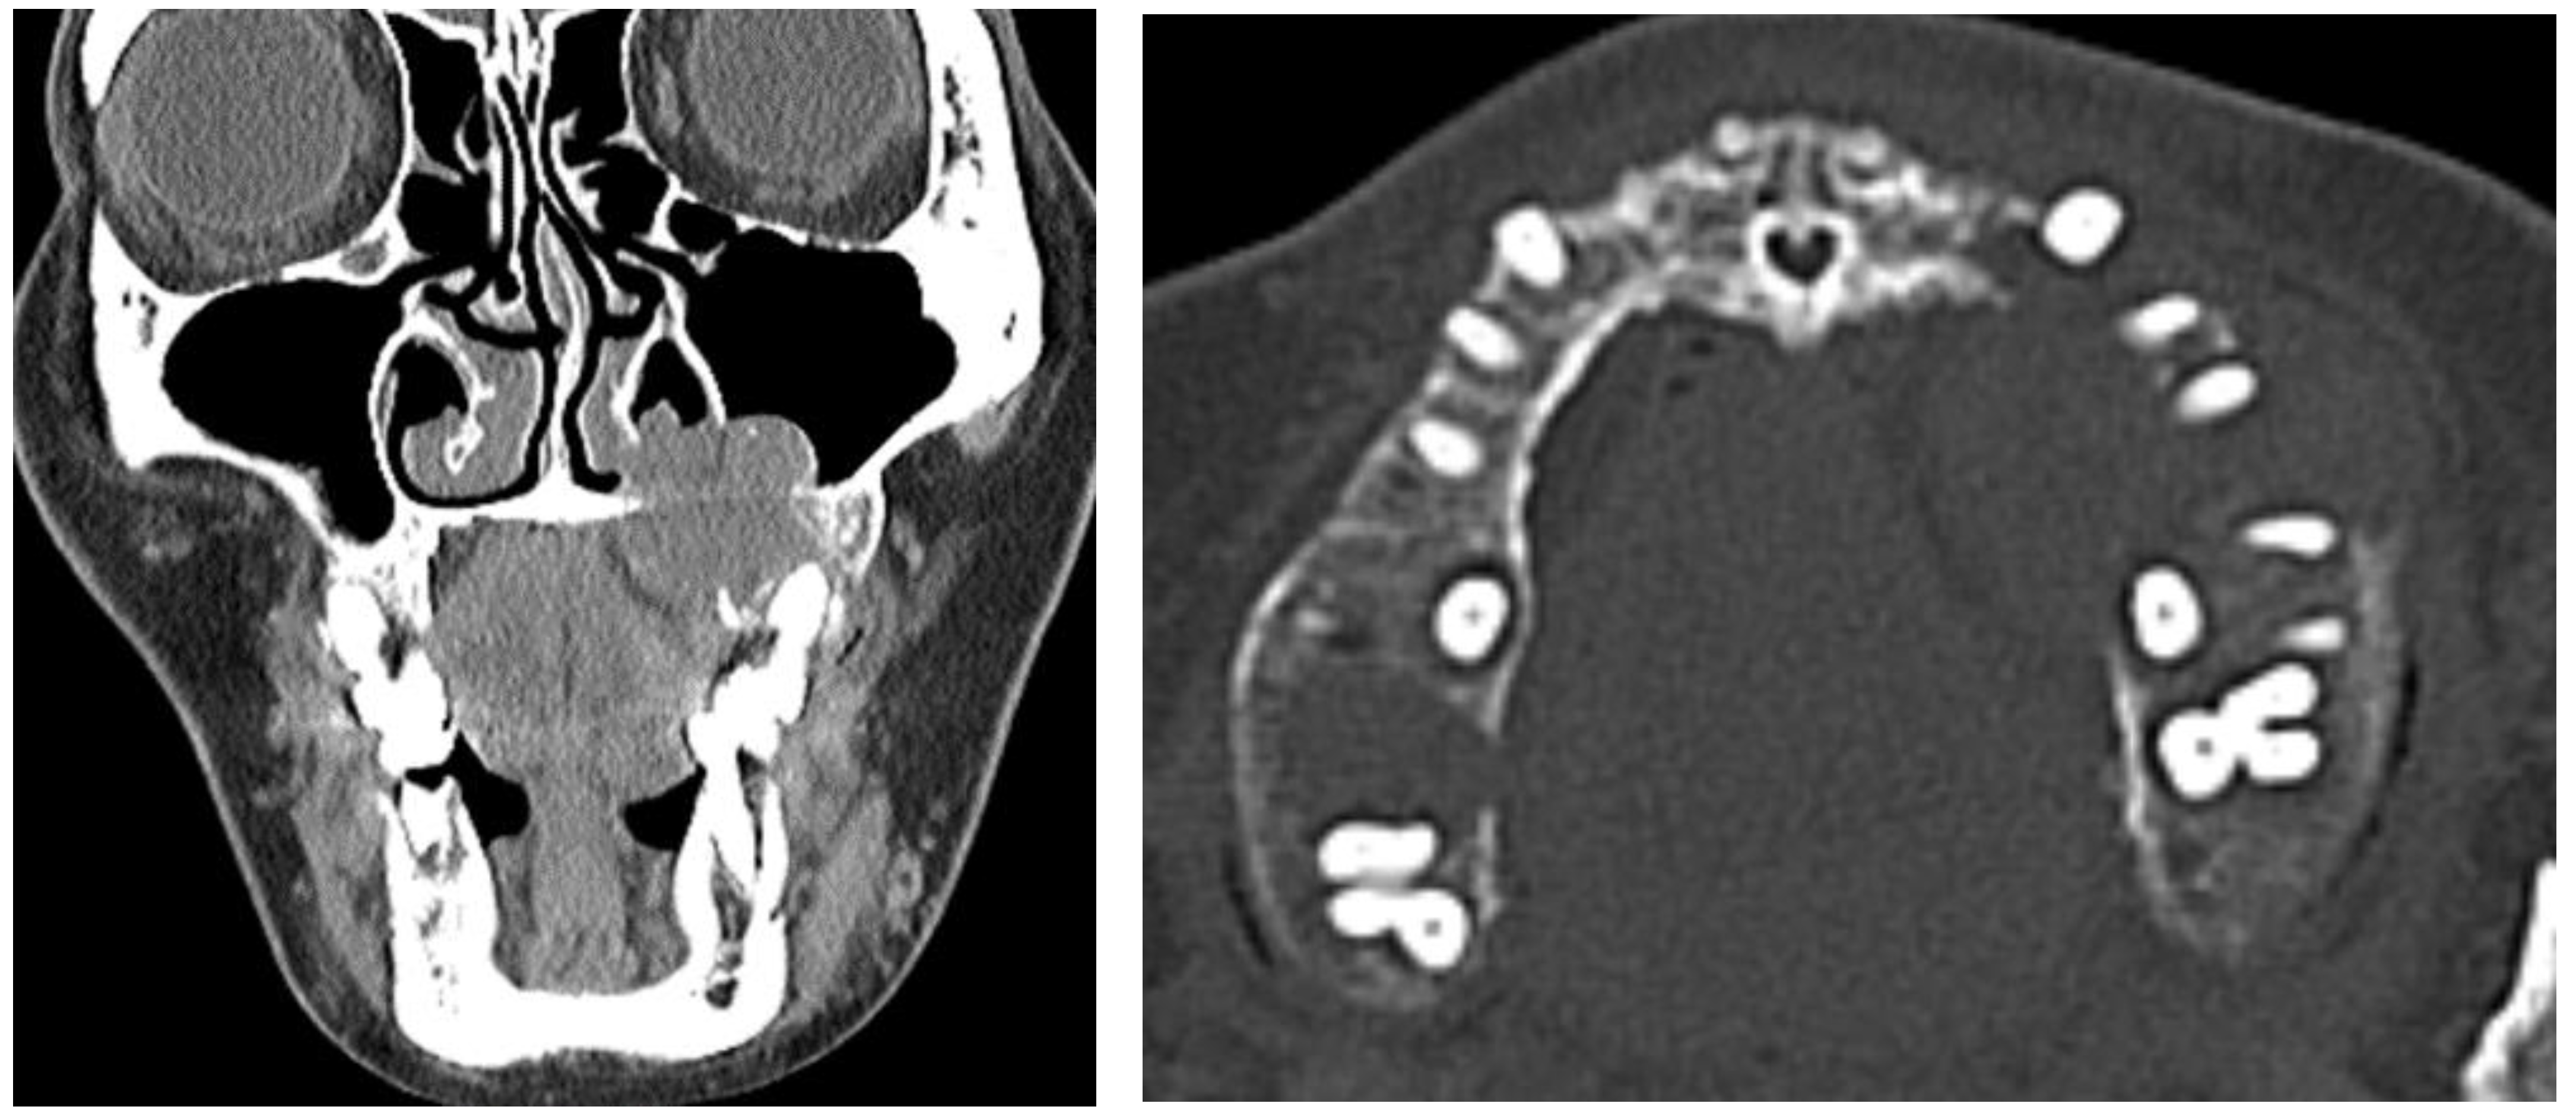

2.3. Diagnosis and Management